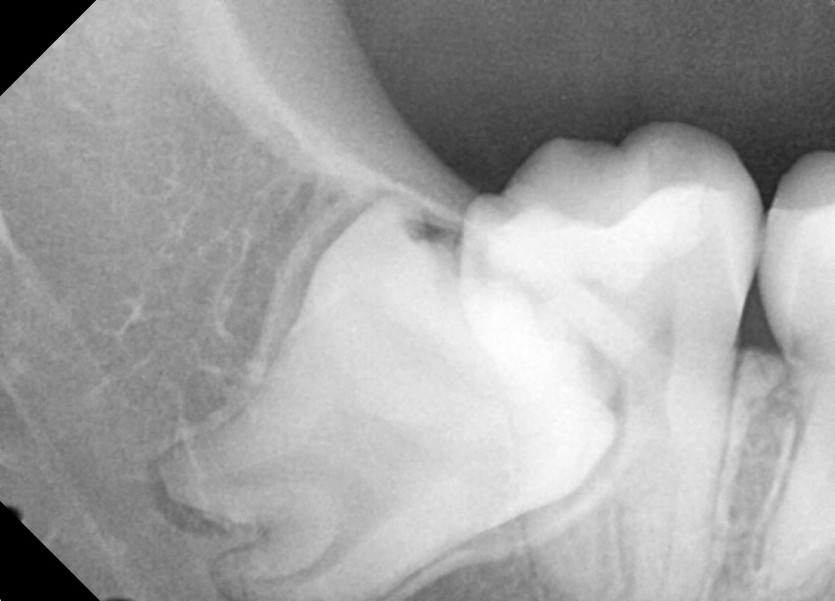

#48 사랑니 발치

구강 외과 전문의가 당일 발치했습니다.